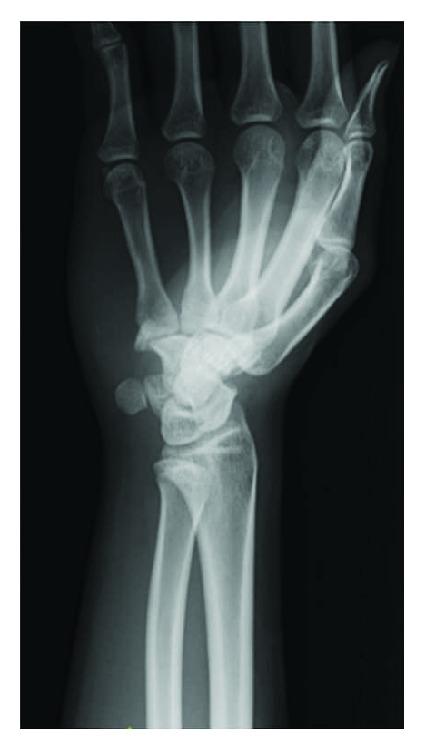

一名水球运动员的钩骨应力性骨折

Stress Fracture of the Hamate Hook in a Water Polo Player.

Hamate hook fractures are usually caused by direct trauma while using a tennis racket or a baseball bat. We report stress fracture of the hamate hook in a water polo player without any specific trauma. We consider that the stress fracture occurred via indirect mechanisms through the flexor tendons. Strong ulnar deviation of the wrist during ball release and strong grip on a ball with outstretched fingers, which are unique to water polo, were the likely causes of the stress fracture of the hamate hook.

钩骨骨折通常是在使用网球拍或棒球棒时受到直接创伤所致。我们报告了一例水球运动员发生的钩骨应力性骨折,该运动员并无任何特定创伤。我们认为,应力性骨折是通过屈肌腱经间接机制发生的。水球特有的在传球时手腕强力尺侧偏斜以及手指伸展时紧握球的动作,可能是钩骨应力性骨折的原因。